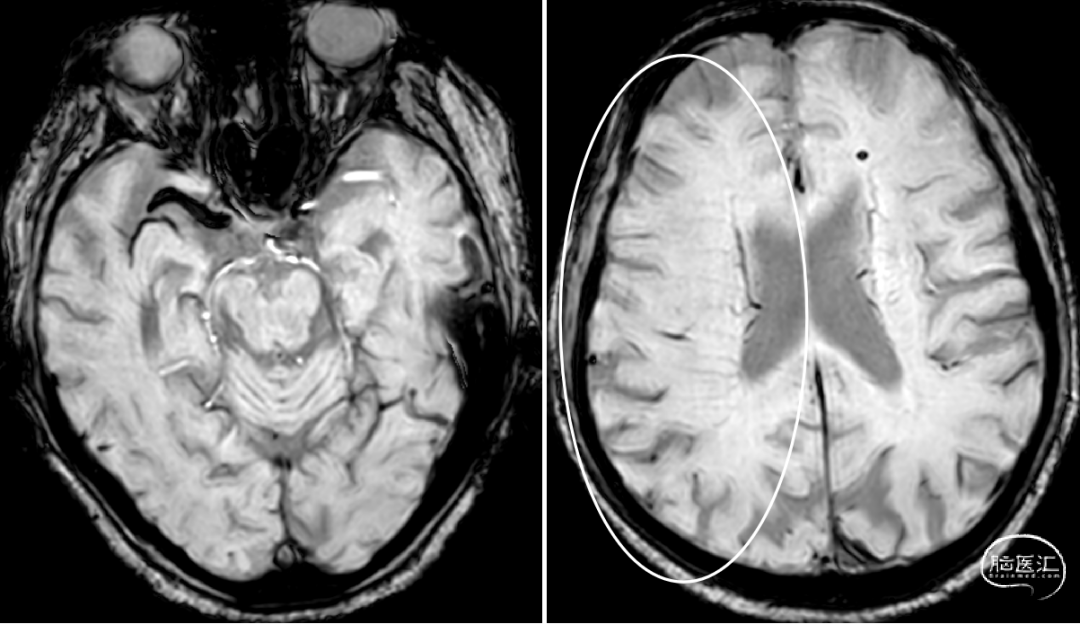

Reexamination Cranial CT:梗死区造影剂渗出。

Reexamination Cranial T2 Flair。

Reexamination Cranial SWI:壳核后部,造影剂渗出最多的地方再灌注损伤。